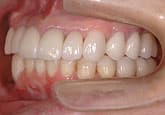

3週間後

さらに正しいはみがき

を行って3週間後

ここまで患者さんが丁寧に歯をみがいただけです。

歯科医と衛生士は何もしていません。